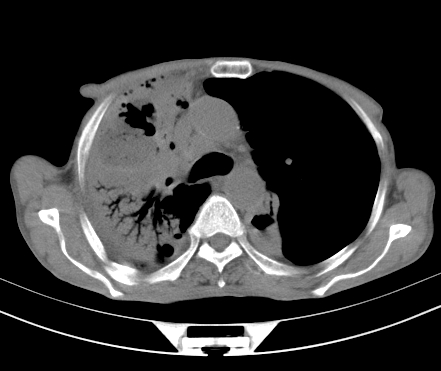

以下是引用gaoshengjiang在2008-5-30 19:53:00的发言:[br]右上叶可见大片实变影,其内可见充气支气管影及囊状影,右上叶尖端支气管走形区可见结节样影,左侧胸腔内可见胸腔胃影。纵隔淋巴结肿大。[br]考虑:1.右上肺阻塞性肺炎伴肺脓肿形成。支持转移所致。[br] 2.左侧胸腔胃。